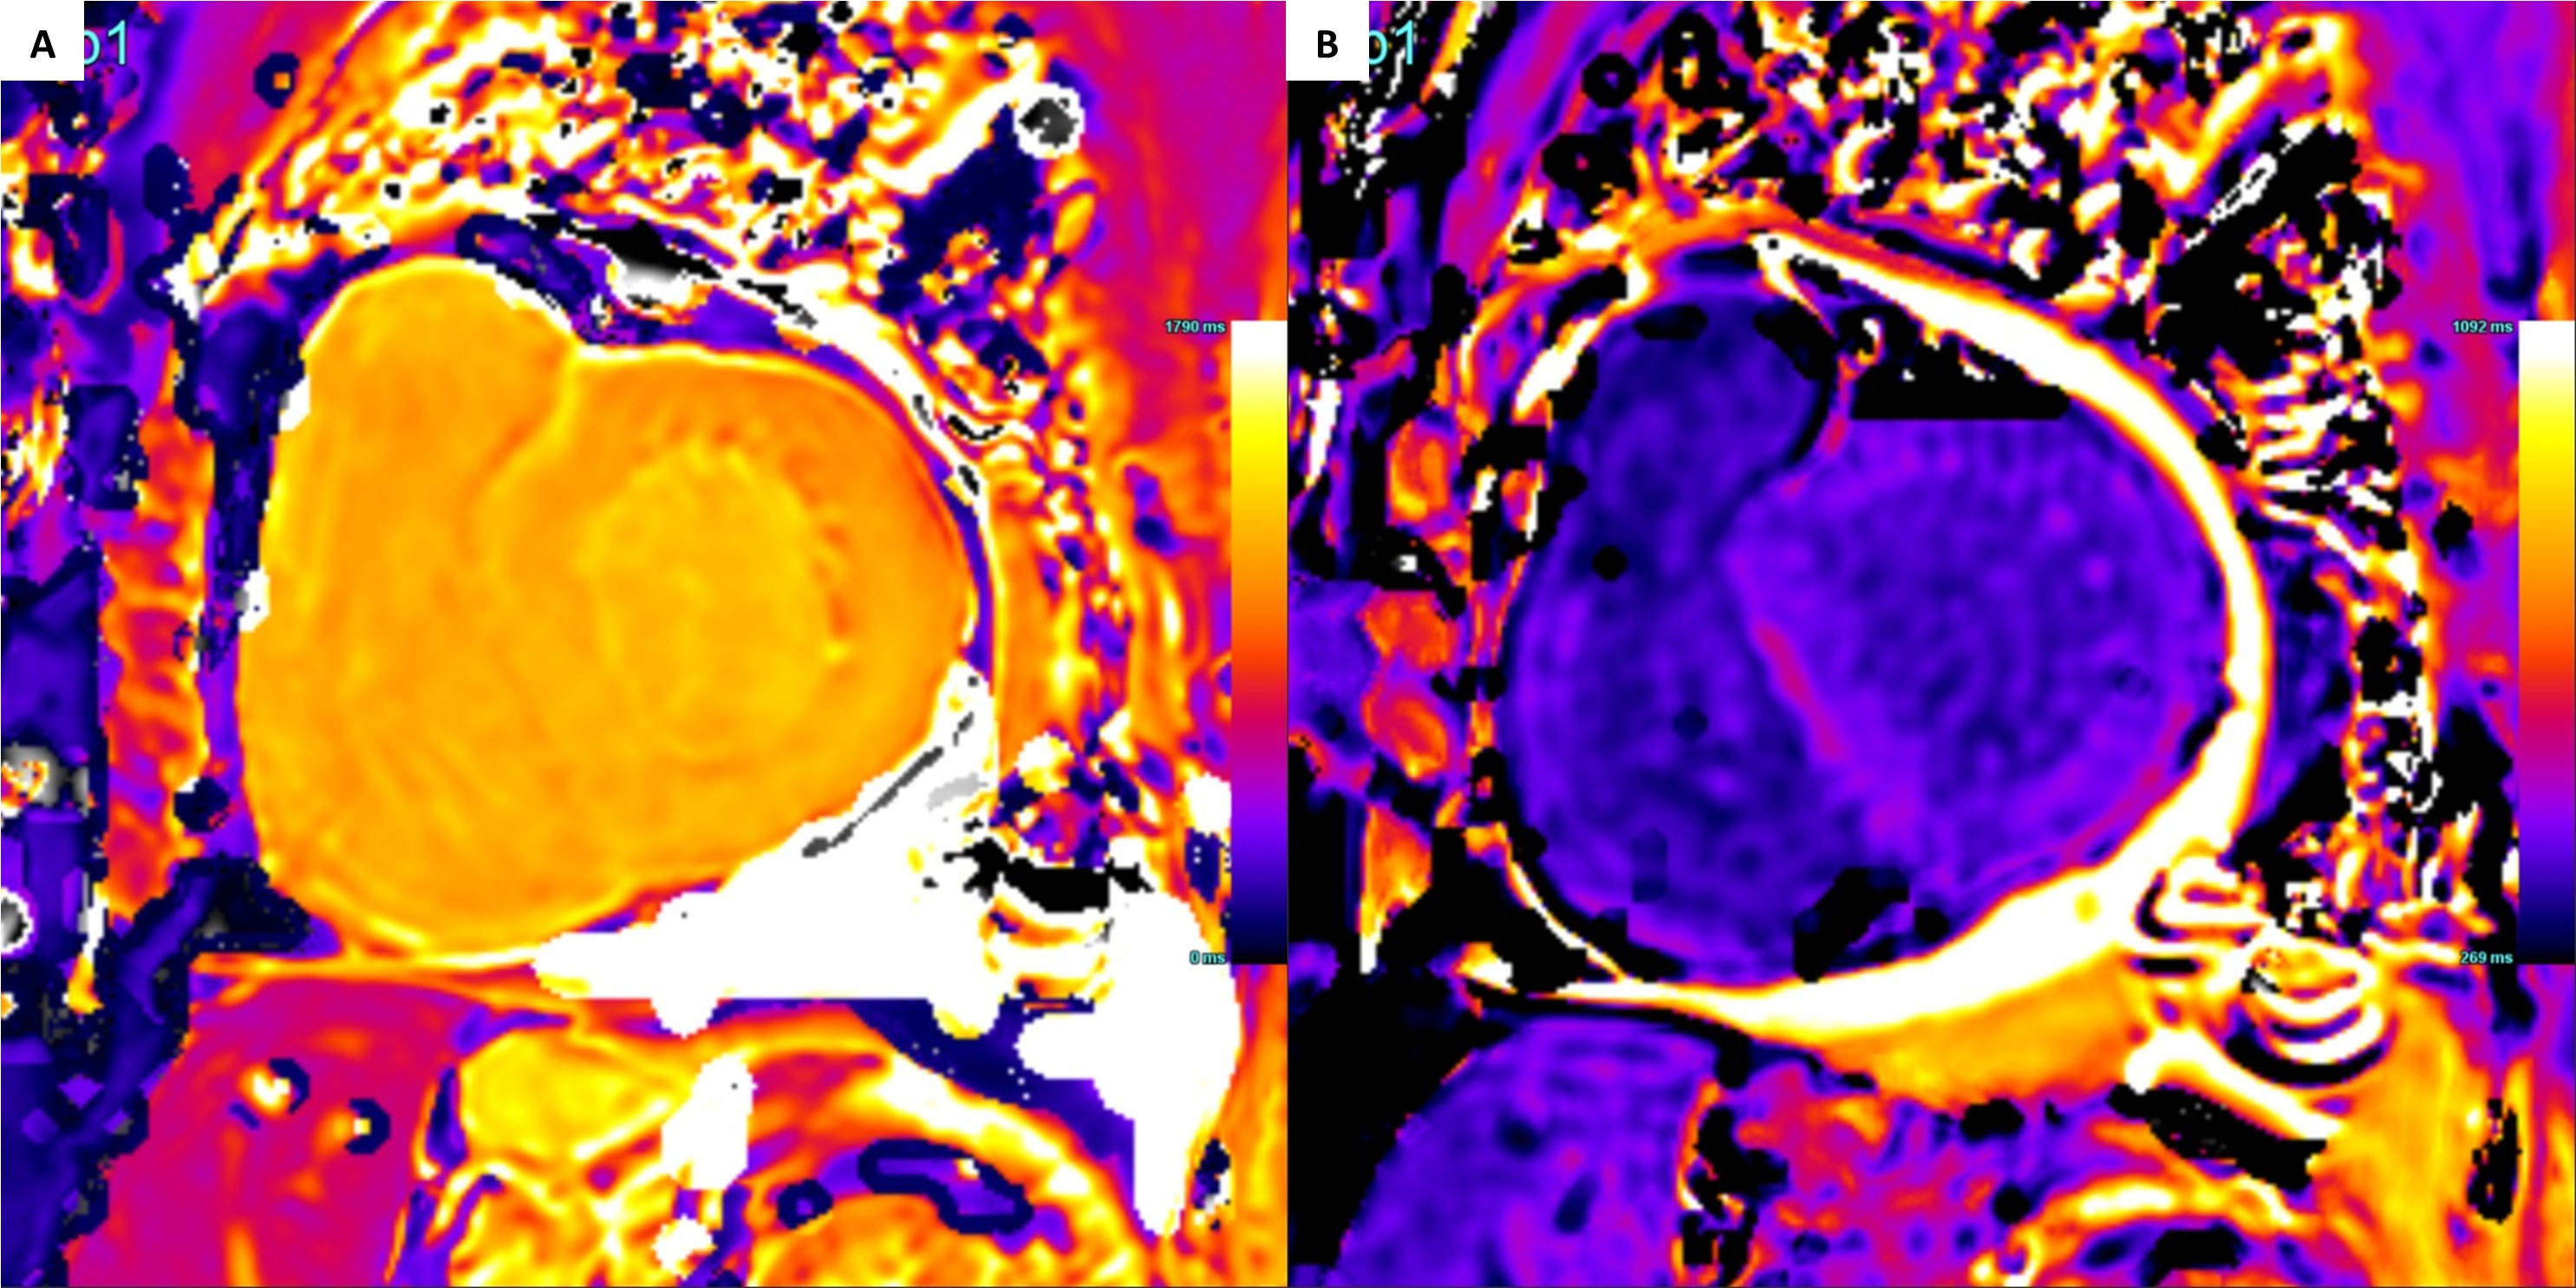

Fig 3. (A) Native T1 mapping of the LV base demonstrating a normal myocardial value of 1132ms and an unexpectedly low blood pool value of 1237ms (Acquired on a 3T machine). (B) Post-contrast T1 mapping of the LV base demonstrating a normal myocardial value of 433ms and blood pool value of 406ms. These myocardial values are inappropriately low for a patient with biopsy confirmed AL amyloidosis given concurrent use of supplemental IV iron.